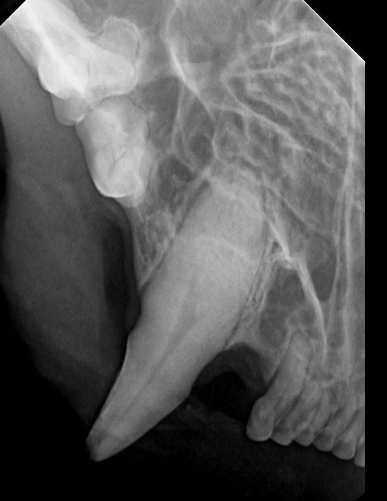

14

Q

DX?

A

fistule cutanée infra-orbitale